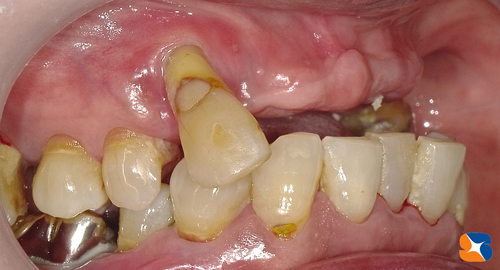

今年11月の初め。70代の患者様。20年来のかかりつけ歯科医院への治療後の帰り道。主訴は「もう吹っ切れた。痛みや腫れを訴えても、歯の掃除と薬だけ。なんかおかしい。たまたま通りかかっただけやけど診て欲しい」でした。

歯の根の周りの骨が大きく溶けて無くなってしまっている所が3箇所。

見た目も正直メチャクチャです。気の毒としかいいようがない。

よく今まで辛抱してきましたね。とにかく私が最短で、全ての悩みを解消いたします。

ビックリするような口元にしますので、任せておいて下さい。

残せる歯と、抜かなければならない歯の区分けが完了しました。

残した歯の治療は全て完了。最後に入れ歯を製作・装着すれば完成です。

12月28日、本日、入れ歯を装着して完了しました。

鏡を見た患者様は顔をくちゃくちゃにして「ここまで綺麗にしてもらえるとは思ってもいなかった。僅か2ヶ月でこんなにいい感じにしてもらえて感謝しています。嬉しくて、嬉しくて、しゃーない。右下の奥歯もずっと無いままで気にしていたので、ここは先生のお薦めのインプラントをしてもらうわ。来年もよろしくお願いします」でした。